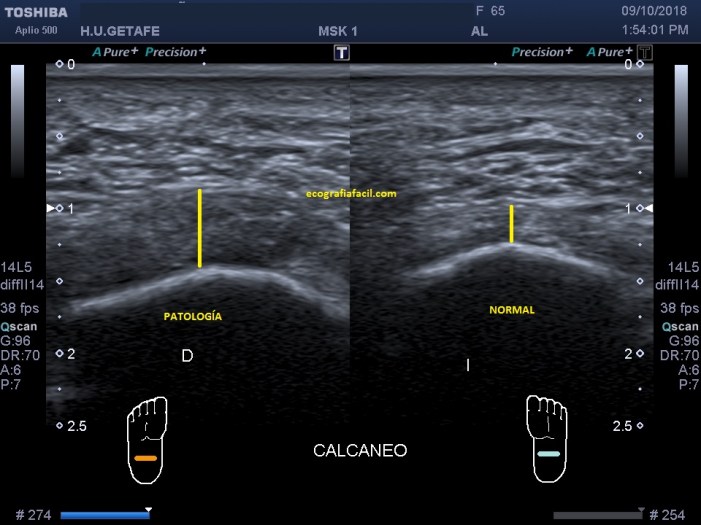

Primero tenemos una imagen en corte longitudinal, vemos normalidad y patología cumpliendo rigurosamente los parámetros de hipoecogenicidad y aumento de calibre en la zona de dolor.

First we have an image in longitudinal section, we see normality and pathology rigorously fulfilling the parameters of hypoechogenicity and increase of caliber in the area of ​​pain.

Segundo, tenemos una imagen en corte axial (observa el picto), vemos normalidad y patología cumpliendo rigurosamente los parámetros de hipoecogenicidad y aumento de calibre en la zona de dolor.

Obsérvense las medidas patológicas con respecto a los estándares de normalidad.

Second, we have an image in axial section (observe the picto), we see normality and pathology rigorously fulfilling the parameters of hypoechogenicity and increase in caliber in the pain area.

Observe the pathological measures with respect to normality standards.